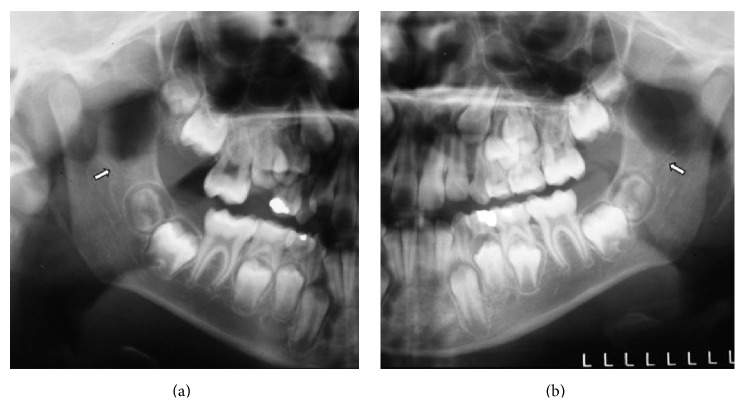

背景。后磨牙管(RMC)是一种解剖变异,可引起牙科手术并发症。方法。根据年龄、性别、两侧下颌副管和下颌副孔的存在情况对500张全景x线片进行RMC评估,这些x线片属于7至20岁的个体。通过Fisher精确检验和Pearson卡方检验研究感兴趣的相关性,通过Pearson相关系数(r)研究相关性,使用显著性水平为5%。结果。44张x线片(8.8%)观察到RMC,其中24位为女性。RMC与年龄无统计学意义(p > 0.05);Fisher精确检验)、性别(p = 0.787;Pearson's Chi-Square检验)、两侧下颌管和颏孔数量(p > 0.05;皮尔逊卡方检验)。RMC与侧位有显著相关性,右侧根管频率较高(p < 0.05;费雪精确检验)。结论。尽管RMC的发生率很低,但其识别和确认其尺寸和路径是相关的,主要是在麻醉和外科手术可能出现失败或困难的情况下。

Background. The retromolar canal (RMC) is an anatomical variation that can cause complications in dental procedures. Method. The RMC was evaluated according to age, sex, and presence of accessory mandibular canal and accessory mental foramen, on both sides in 500 panoramic radiographs, belonging to individuals at the age of 7 to 20 years. The associations of interest were studied through Fisher's Exact Test and Pearson's Chi-Square Test, and the correlation was studied through Pearson's Correlation Coefficient (r). The significance level used was 5%. Results. The RMC was observed in 44 radiographs (8.8%), and out of those 24 were females. There was no statistically significant association between the RMC and age (p > 0.05; Fisher's Exact Test), sex (p = 0.787; Pearson's Chi-Square Test), amount of mandibular canals and mental foramina, on both sides (p > 0.05; Pearson's Chi-Square Test). There was a significant association between RMC and side, the higher frequency of the canal being on the right side (p < 0.05; Fisher's Exact Test). Conclusions. Despite the low occurrence of the RMC, its identification and the verification of its dimensions and path are relevant, mainly in cases when anesthetic and surgical procedures can present failures or difficulties.